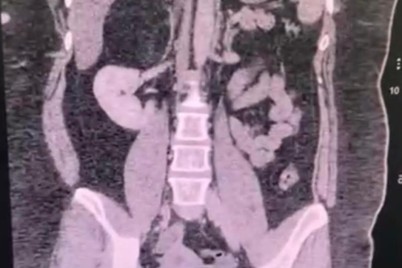

جدة - سلطان السلمي تمكّن فريق طبي بقيادة استشاري جراحة التجميل والجراحات الميكروسكوبية، رئيس وحدة جراحة التجميل بمستشفى الملك عبدالعزيز...